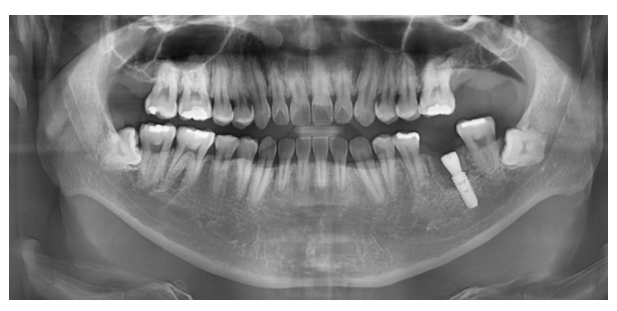

파노라마 X-ray

230622

240125